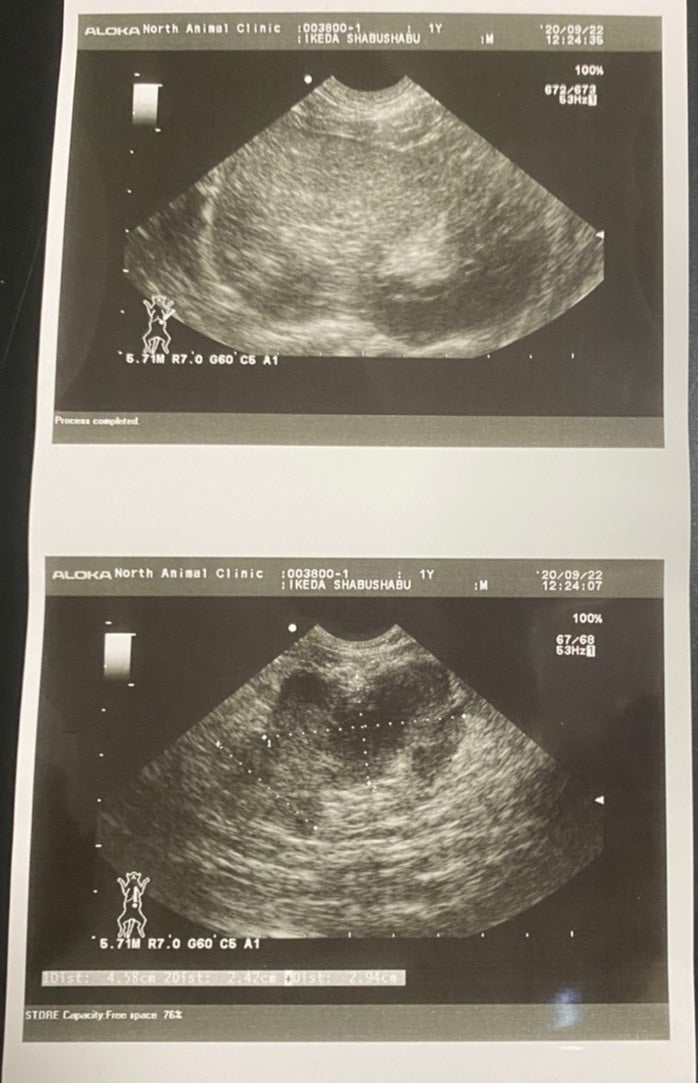

22日 未承認薬での治療のため違う病院へ。FIPドライタイプ 中期と診断。検査と7日分の未承認薬を購入222,970円 計 366,602円

(腹部に4cmの腫瘍が見つかりました。)

(血液検査の結果です。総ビルリビンとA/G比、白血球数の数値から、FIPと診断されました。)